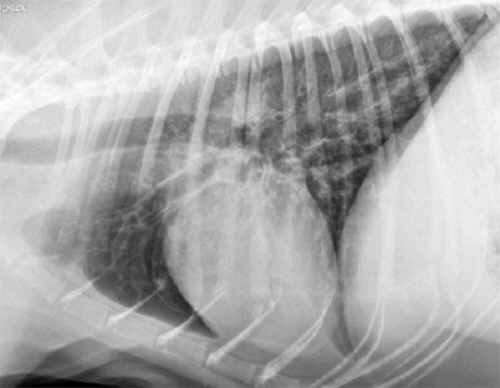

Бронхит - воспаление бронхиального древа. Основным симптомом является кашель, затруднение дыхания и характерные изменения на рентгенограмме легких. Однако, заболевания легких у кошек, протекающие как бронхит, могут быть различной природы: обструктивными (хронический обструктивный бронхит), или вызванными аллергией (астма кошек), иметь в качестве причины внешний агент (бактерии, вирусы).

В зависимости от наблюдаемых симптомов, ветеринарный врач может провести ряд тестов для определения диагноза и выполнить несколько базовых исследований (анализ мочи, биохимический анализ крови, кала, или общий клинический анализ крови). Другие тесты могут включать тест на дирофиляриоз (сердечные гельминты), вирус лейкоза кошек и вирус иммунодефицита, рентгенографию грудной клетки, некоторые вирусологические исследования.